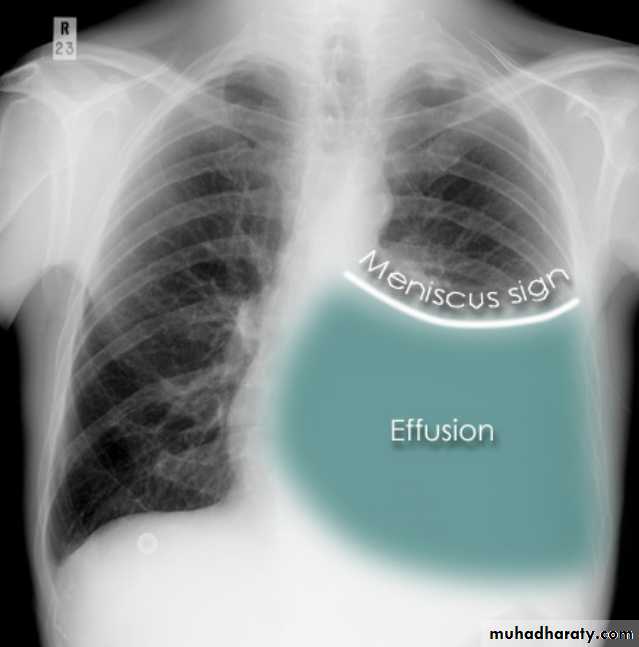

Chest imaging -2Pleural effusionPleural effusion tends to be used as a catch-all term denoting a collection of fluid within the pleural space. This can be further divided into exudates and transudates depending on the biochemical analysis of aspirated pleural fluid. Essentially it represents any pathological process which overwhelms the pleura's ability to reabsorb fluid.

Radiographic appearances

Plain radiograph

Chest radiographs are the most commonly used examination to assess for presence of a pleural effusion, however it should be noted that on a routine erect chest x-ray as much as 250-600 ml of fluid is required before it becomes evident 6. A lateral decubitus film is most sensitive, able to identify even a small amount of fluid. At the other extreme, supine films can mask large quantities of fluid.

Both PA and AP erect films are insensitive to small amounts of fluid. Features include:

blunting of the costophrenic angle

blunting of the cardiophrenic angle

fluid within the horizontal or oblique fissures

eventually a meniscus will be seen, on frontal films seen laterally and gently sloping medially

A subpulmonic effusion (infrapulmonary effusion) may be seen when there is previously established pulmonary disease, but can also be encountered in normal lungs , They are more common on the right, and usually unilateral

with large volume effusions, mediastinal shift occurs away from the effusion (note: if coexistent collapse dominates then mediastinal shift may occur towards the effusion)